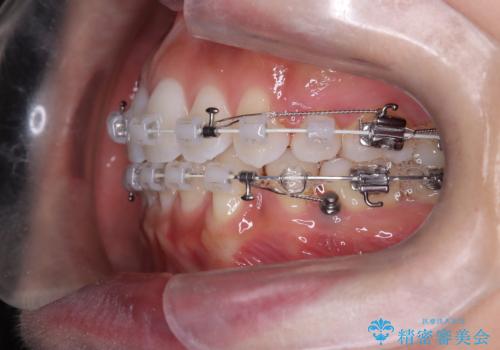

上下左右の小臼歯を抜歯後、ワイヤー矯正装置を装着し、全体のバランスを見ながら歯を移動させていきました。特に前歯の後方移動では、抜歯スペースを活かして口元を内側に下げることに重点を置きました。また、八重歯も時間をかけて丁寧に整列させ、左右の正中(真ん中の位置)もぴったりと揃えることができました。